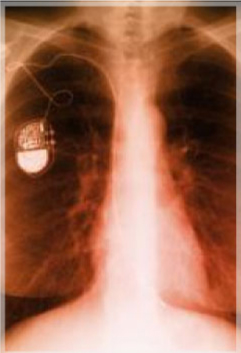

Asociación Americana del corazón Instituto Nacional de Salud de los Estados Unidos Marcapasos, desfibriladores, válvulas ENTREVISTA DE TELEVISIÓN

Métodos de Diagnóstico Cardiovascular